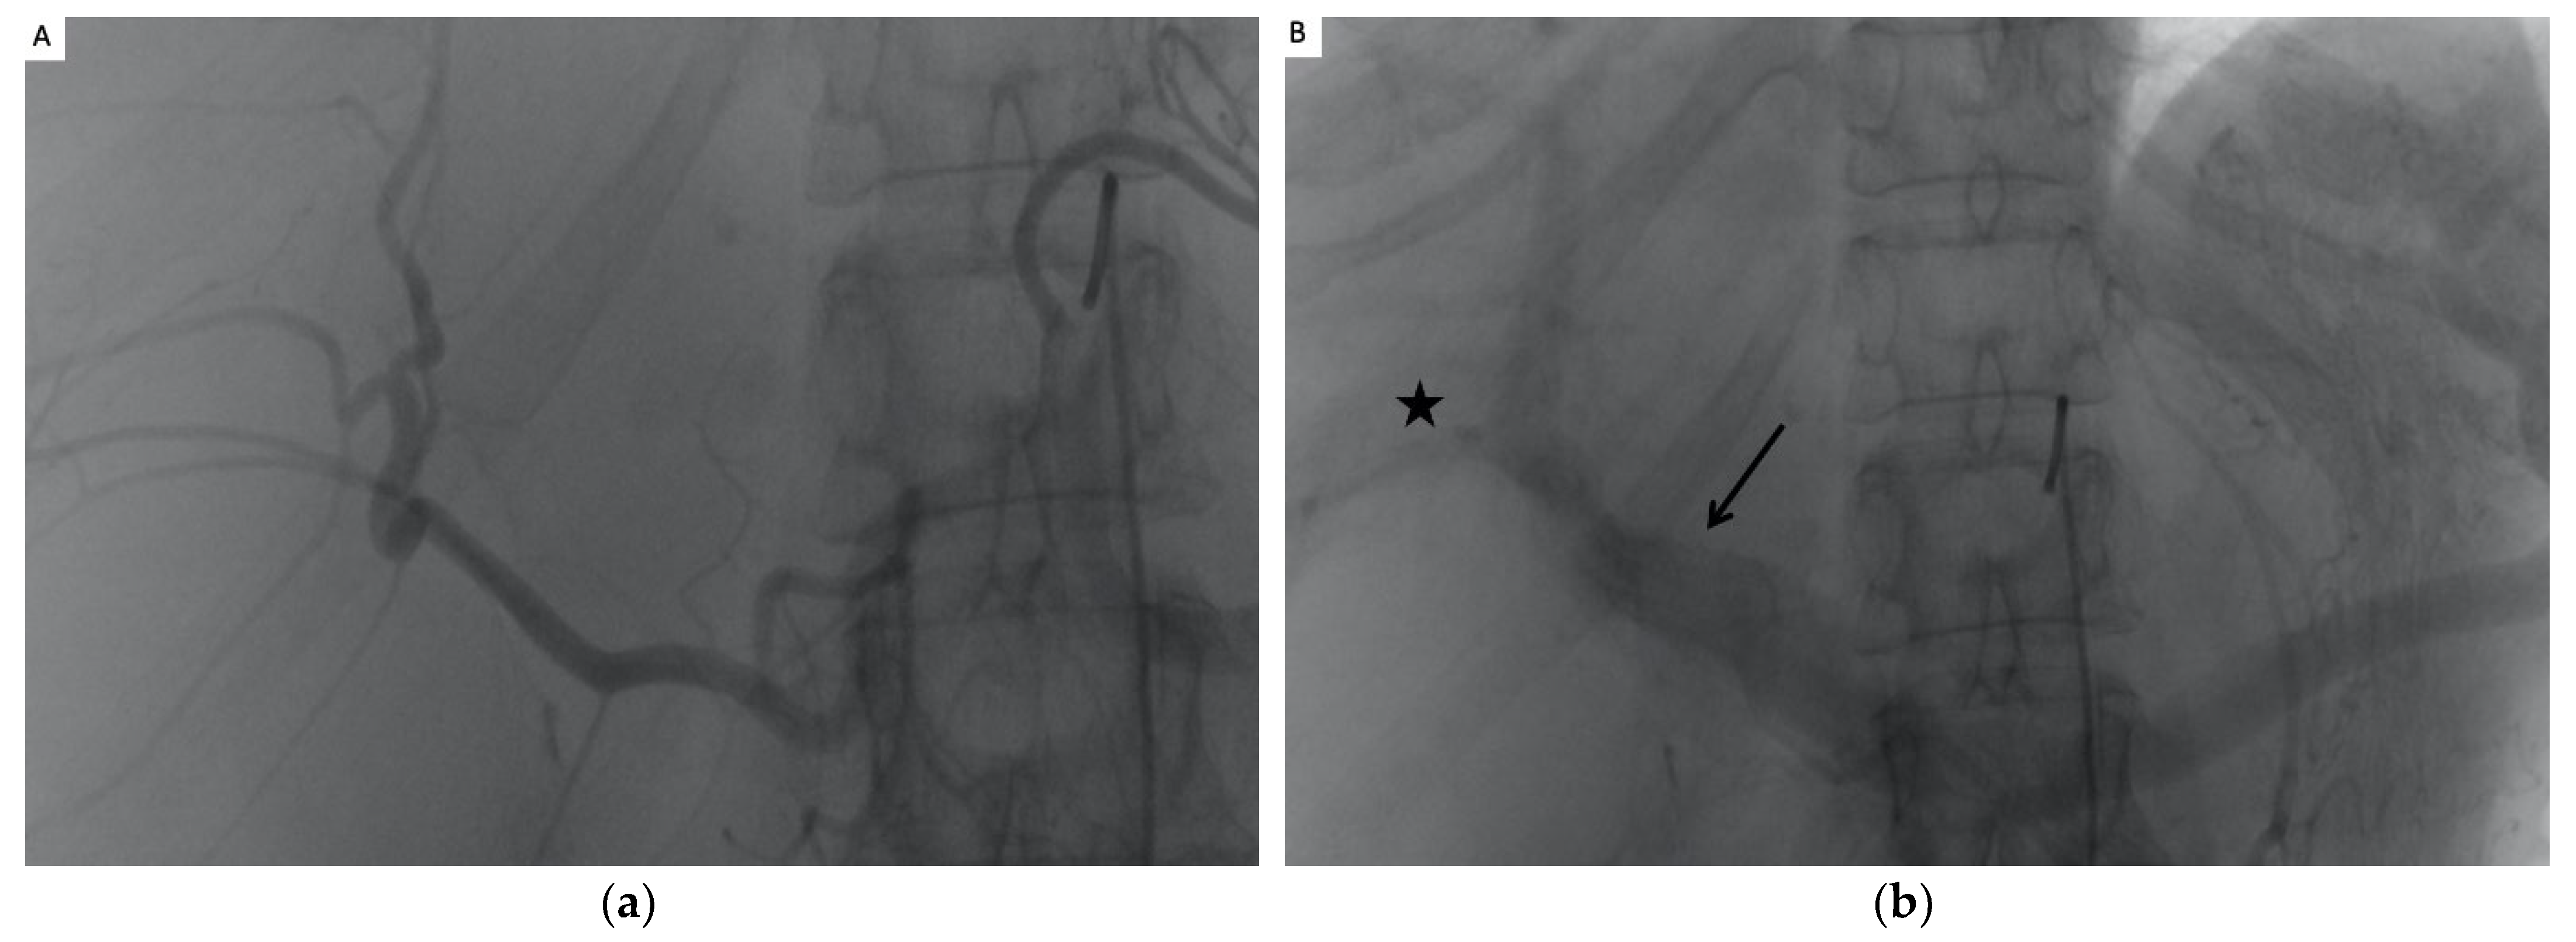

2.3. The TAE Procedure

3.2. Technical Success